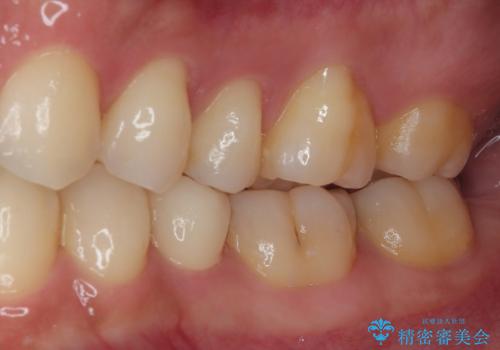

フロスがちぎれることもなくなり、被せものが入っていることを忘れていたと大変喜んでいただきました。適合の良い被せものは二次的な虫歯の再発リスクを低減してくれます。

今後の予定は患者様のタイミングで歯茎から少し見えている親知らず抜歯を行っていく予定です。